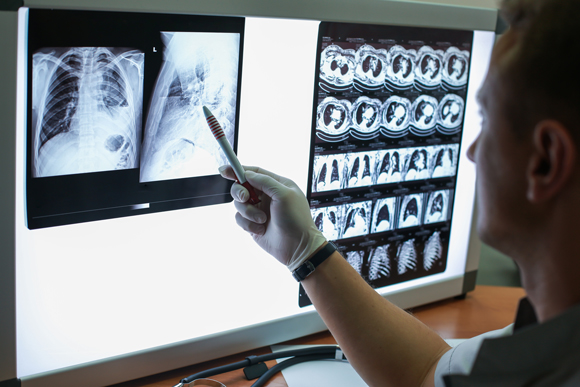

تعتمد العديد من التّشخيصات الطّبّيّة على تفكيك صور التّصوير التّشخيصيّ الطّبّيّ وتفسيرها مثل الأشعة السّينيّة، التّصوير المقطعيّ (CT) والتّصوير بالرّنين المغناطيسيّ (MRI). يتمّ التّشخيص من قبل أطباء متخصّصين في تفسير صور التّصوير التّشخيصيّ، وتحديد التّشخيص الطّبّيّ المحدّد. أيّ، لفكّ رموز صور التّصوير التّشخيصيّ، وتحديد التّشخيص الطّبّيّ بناءً عليها، هناك حاجة إلى رجل أو امرأة محترفين خضعوا لتدريب مكثّف.

في السّنوات الأخيرة، بدأ استخدام التّطوّرات التّكنولوجيّة في مجال التّعلّم الآليّ، لتحليل صور التّصوير الطّبّيّ – بنجاح باهر. يتمّ إجراء التّشخيص المبكّر لسرطان الثّدي، على سبيل المثال، بمساعدة الأشعة السّينيّة لأنسجة الثّدي، والتي تسمى تصوير الثّدي الشّعاعيّ (Mammography). نجحت خوارزميّات الذّكاء الاصطناعيّ في تحديد المناطق المشبوهة في صور تصوير الثّدي الشّعاعيّ، ممّا ساعد الأطباء على إجراء تشخيصات دقيقة. في التّجارب الّتي استعان الأطباء بالذّكاء الاصطناعيّ لتشخيص سرطان الرّئة، حقّقوا معدّل خطأ أقلّ عندما أشار الذّكاء الاصطناعيّ إلى مناطق مشبوهة في الصّور الشعاعيّة.

كان جيفري هينتون (Hinton)، أحد آباء الذكاء الاصطناعيّ الحديث، سابقًا لعصره في ثقته بقدرات هذه الآليّة. في مؤتمر عقد في عام 2016، دعا هينتون إلى إنهاء تدريب أطباء الأشعة. من الواضح – كما زعم – أنَّ الذكاء الاصطناعيّ سيتفوّق على قدرات أخصائيّي الأشعة، في غضون 5 إلى 10 سنوات. في وقت لاحق، راجع هينتون توصيته: ليس من المجديِّ الاستسلام لأخصائيّي الأشعة، ولكن المضيّ قدمًا نحو وضع يقرأ فيه الذّكاء الاصطناعي صور التّصوير لأخصائيّي الأشعة.

يمكن أن يساعد الذّكاء الاصطناعيّ الأطباء في تشخيص الأمراض بناءً على صور التّصوير الطّبّيّ. صورة تصوير لمريض الرئة | Egor_Kulinich, Shutterstock